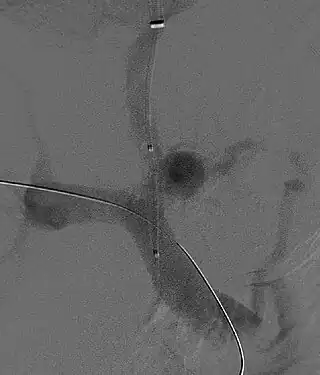

![]() Imagen fluoroscópica de un DPIT en curso. Se ha introducido un catéter en la vena hepática y, tras la punción con aguja, se ha introducido una guía metálica en una rama de la vena porta. El tracto se dilató con un globo y se inyectó contraste. Sobre el alambre se ha colocado un stent metálico autoexpandible. | ||

Se realiza una pequeña incisión en el cuello para tener acceso a la vena yugular interna derecha en la cual se va a introducir una aguja con una sonda flexible (catéter), en su extremo hay un stent de malla metálica y un globo. El médico guía el catéter hasta la vena hepática mediante imágenes obtenidas por rayos X y la inyección de un medio de contraste hace que la vena se vea con mayor claridad.

Si no se logra ver la vena porta a pesar del medio de contraste se puede utilizar la inyección de CO2 debido a que este gas se difunde con facilidad por el parénquima hepático. En el momento en el que se cateteriza la vena suprahepática, se realiza la punción directa al parénquima a través del introductor mediante fluoroscopia, en dirección anteromedial se introduce la aguja y se avanza entre 4 o 5 centímetros hacia la vena porta, la punción también puede ser guiada por ultrasonido para facilitar el acceso. En el momento en el que se crea una comunicación entre la vena hepática y la vena porta (porción intrahepática) se infla el globo para colocar el stent y mantener la derivación permeable.